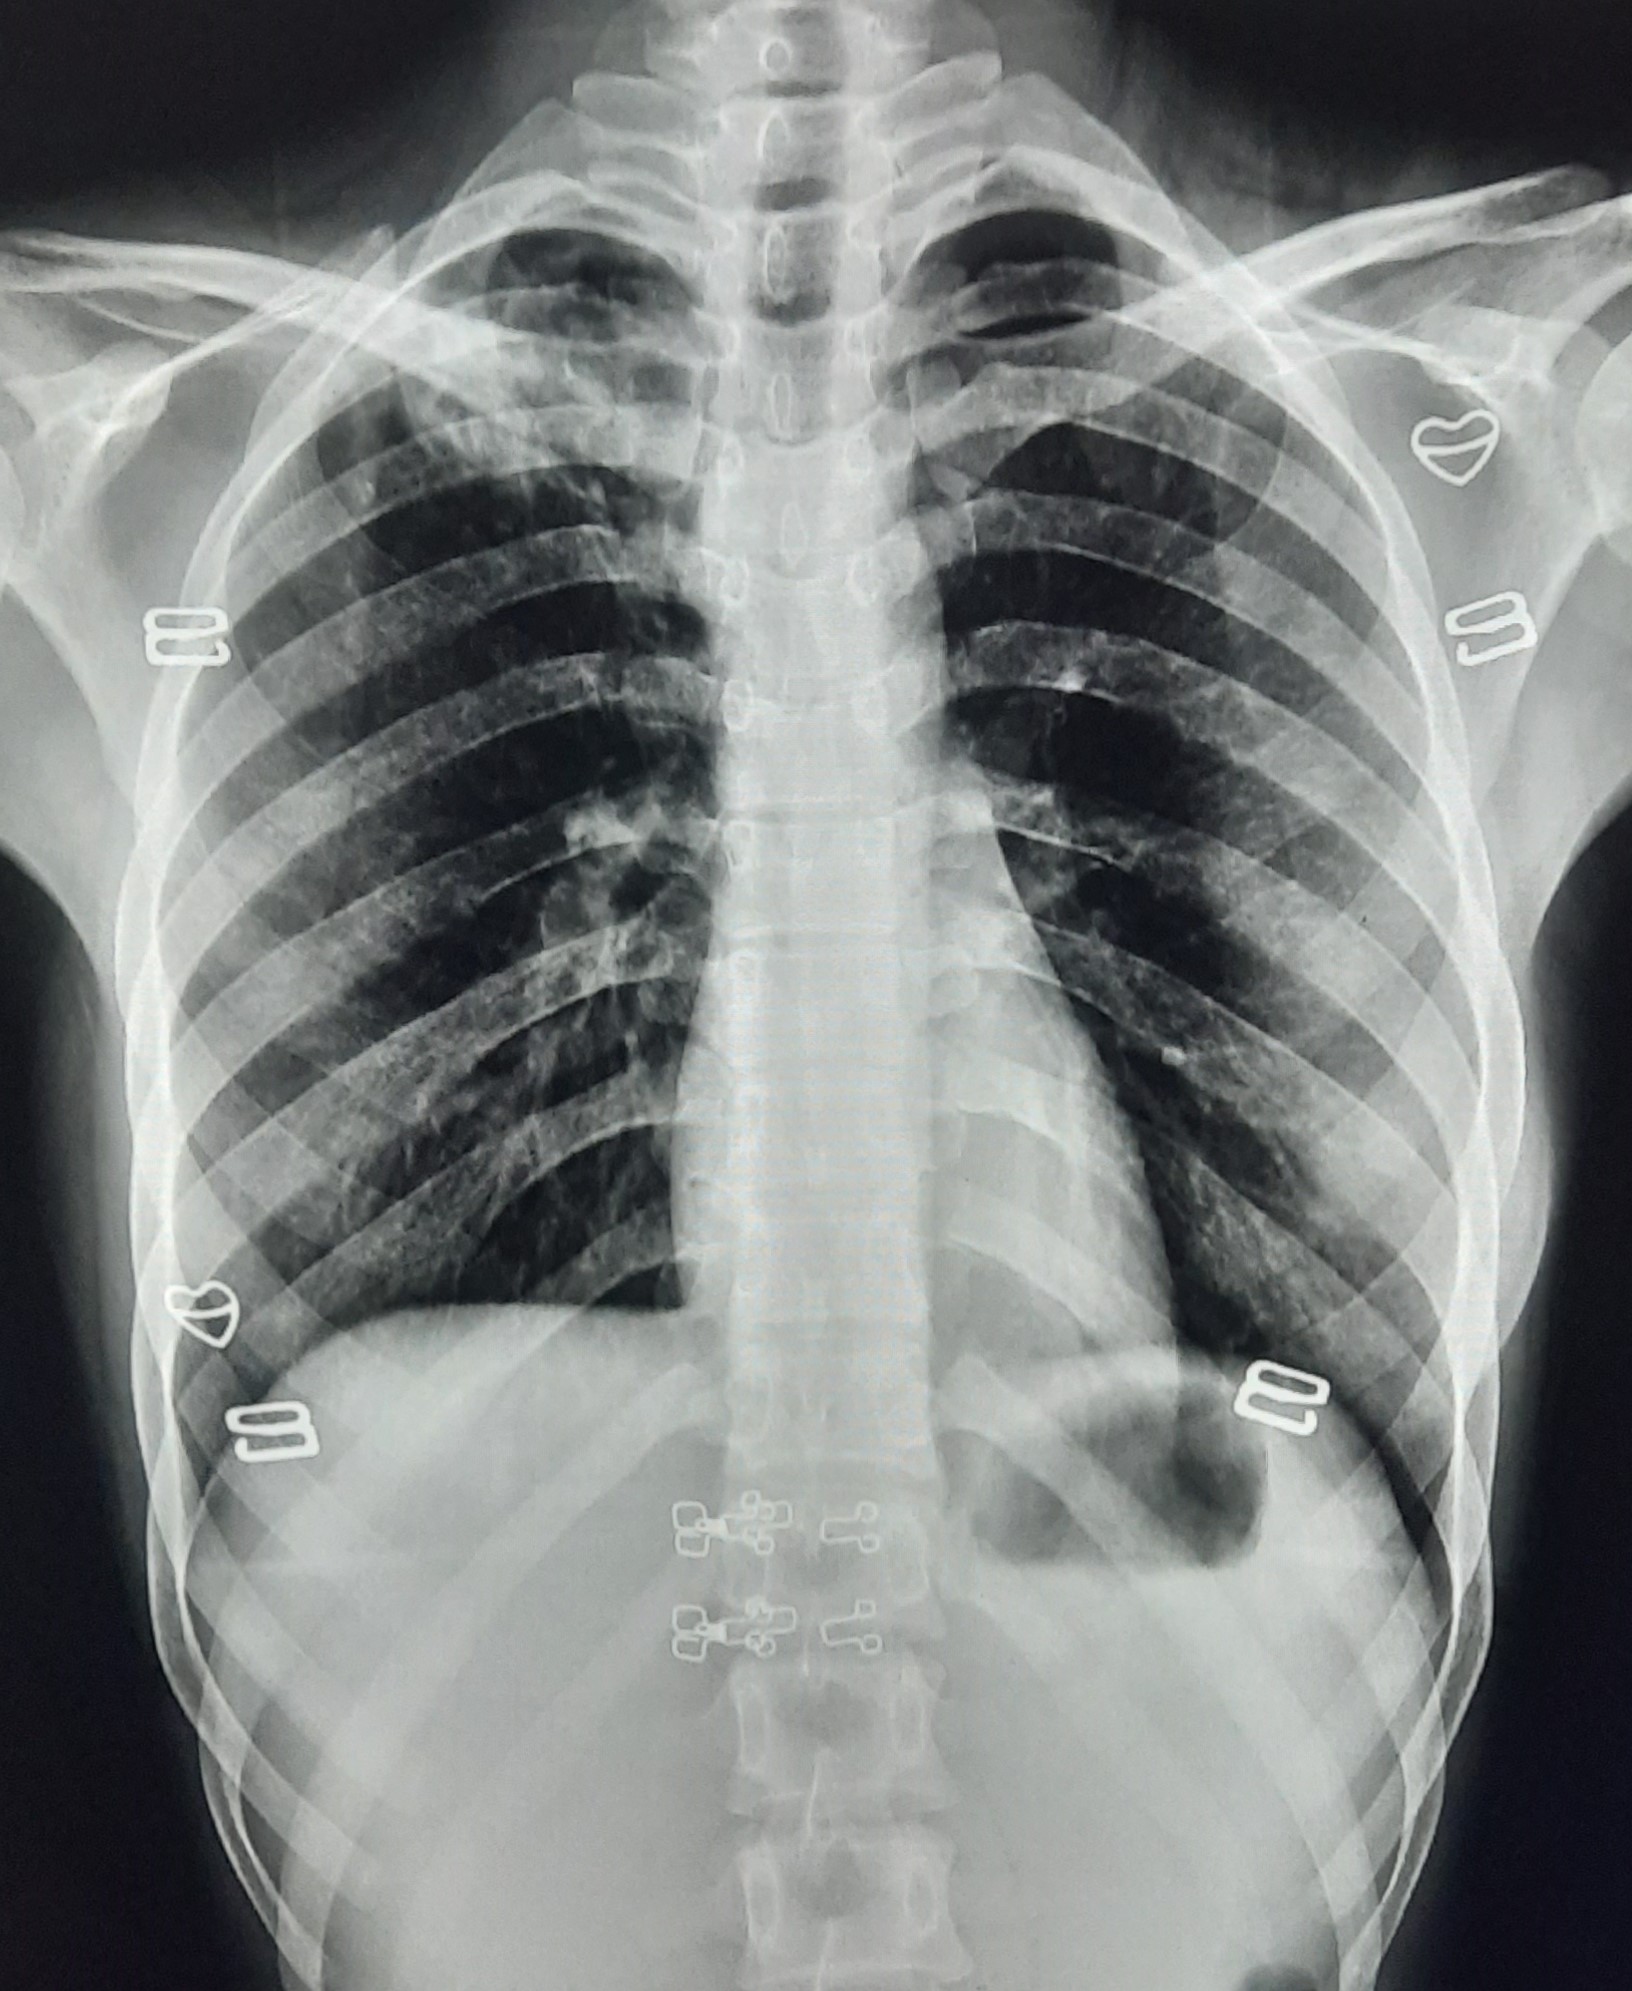

| 132 | IGGMC, Nagpur, Nagpur | P2 | 29-4340 | Ritesh Chaudhary | Consent taken on Paper | 30 Yrs. |

Provisional Diag : Post TB Sequelae

Final Diag : Post TB sequalae With Fibro Cavitary Changes |

Post TB Sequelae | Bilateral Upper Zone Fibro Cavitary Changes With Right Upper Zone Fungal Ball With Bilateral Haziness With Tenting Of Diaphragm | Abnormality visible on x-ray |